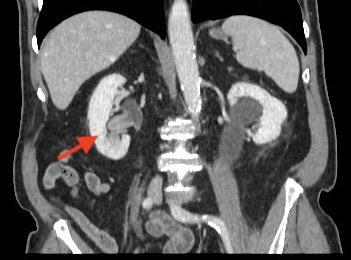

La urografía por tomografía computarizada (TC) – Uro TAC en nuestro país – es actualmente la técnica de imagen más precisa para el diagnóstico del CVUA, siendo de esta manera considerada como el estándar (Figuras 1 y 2)19. La TC puede ayudar además a predecir la etapa T del tumor primario (precisión hasta del 88%), siendo útil en la detección de metástasis regionales y a distancia (para esto último debe incluirse siempre una TC de Tórax)20. Sin embargo, presenta deficiencias en la detección de lesiones planas y tumores <3mm (hasta 40% de sensibilidad), casos en los cuales habitualmente es necesaria una evaluación endoscópica complementaria21. La TC con emisión de positrones (PET) constituye una alternativa promisoria para la evaluación de metástasis a distancia, con una sensibilidad superior a la TC convencional en estudios iniciales (85 vs. 50%), sin embargo requiere más validación para recomendar su uso rutinario en el estudio del CVUA22.

La técnica de URS flex para el diagnóstico de CVUA merece algunas consideraciones especiales (ver video adjunto). Cada vez que sea posible debería intentarse una inspección inicial “sin tocar” el uréter previamente. Es decir, sin introducir una guía hasta la pelvis renal antes de iniciar la ureteroscopía. Esto permite visualizar lesiones a lo largo de todo el uréter y en el sistema colector intrarrenal sin el artefacto o hemorragia que potencialmente pudiera causar la manipulación previa (Figura 3). Para acceder al tracto superior generalmente es necesario, eso sí, al menos dilatar el orificio ureteral y el uréter distal con un ureteroscopio semirrígido o un dilatador (secuencial, coaxial o balón) sobre una guía apenas insinuada. No existe evidencia suficiente para recomendar el uso rutinario de vaina de acceso ureteral, aunque ésta puede facilitar la toma de múltiples muestras para biopsia37.